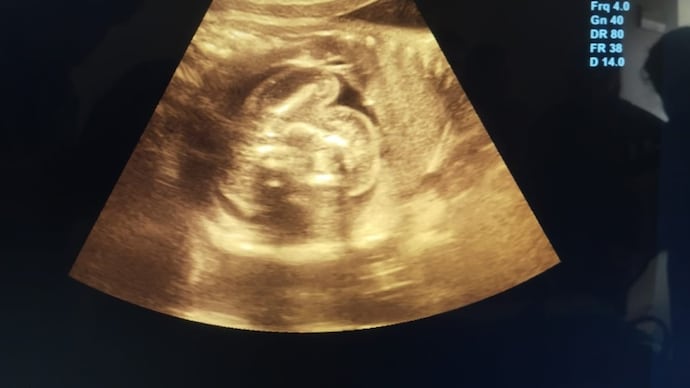

Upon arriving at the hospital, Emma was admitted for monitoring. While reviewing her latest ultrasound, doctors noticed something unusual: a second, smaller amniotic sac adjacent to the main one. Confused and intrigued, the medical team prepared for what they assumed was an unusual presentation of twins.

As the delivery began, doctors carefully navigated the birth of Emma’s healthy baby girl. However, what followed next left the entire team stunned. Inside the secondary sac was what appeared to be an underdeveloped fetus that had stopped growing early in gestation.

This rare occurrence, known in medical terms as “fetus in fetu,” happens when a twin embryo is enveloped by its sibling during the early stages of pregnancy. The enveloped fetus does not develop fully and typically remains undetected unless it causes complications or is discovered incidentally.

Fetus in fetu is an extremely rare condition, estimated to occur in less than 1 in 500,000 live births. Unlike conjoined twins, where both fetuses grow simultaneously and are partially fused, fetus in fetu involves one fetus becoming encapsulated within the body or womb of the other. In most cases, the underdeveloped fetus is discovered during infancy or early childhood, usually as a mass in the abdomen.

However, in Emma’s case, the discovery happened at birth, making it even more uncommon. The encapsulated fetus had its own amniotic sac and had stopped developing several months into the pregnancy. It posed no risk to Emma or her baby and was removed safely during the delivery procedure.